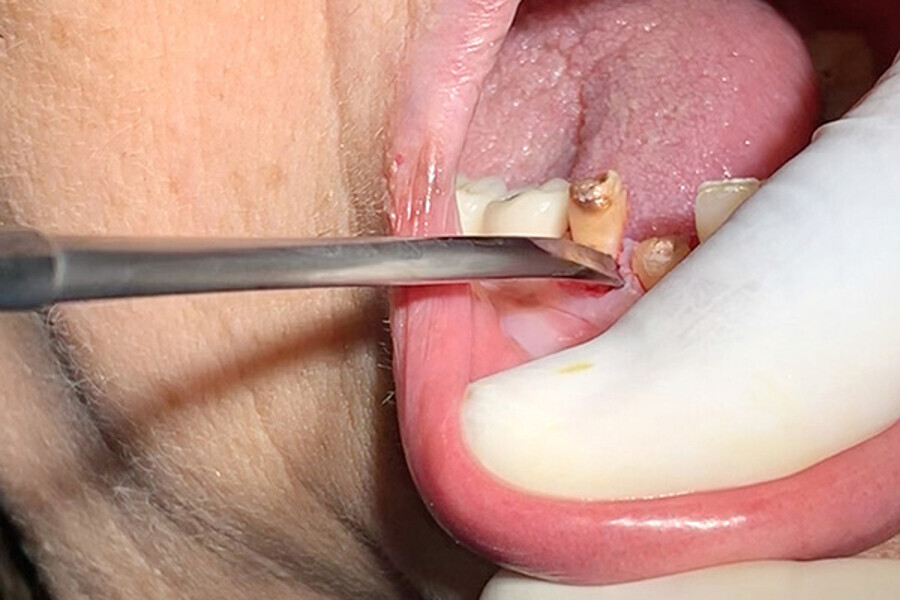

Figs. 4. Uso de los finos insertos para crear espacio entre hueso, ligamento y diente.

Figs. 5. Uso de Botador fino para complementar la luxación.

Figs. 6. Uso de Botador fino para complementar la luxación.